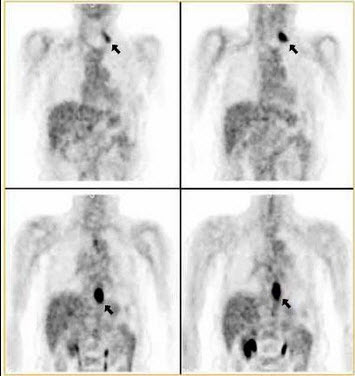

15、单项选择题

54岁男性,进食吞咽有梗阻感半年,行18F-FDG显像如图,诊断是()

A.胃癌

B.胃癌伴锁骨上淋巴结转移

C.食管癌伴锁骨上淋巴结转移

D.喉癌伴纵隔淋巴结转移

E.以上都不是